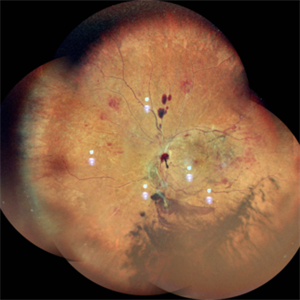

Exudative Retinal Detachment secondary to Leber's Miliary Aneurysm in a case of Retinitis Pigmentosa

Oct 13 2022 by Vaidehi Sathaye

Fundus Photograph of RE of a 23 year male patient , with an Exudative Retinal Detachment secondary to Leber's Miliary Aneurysm in a case of Retinitis Pigmentosa.

Photographer: Dr. Vaidehi Sathaye

Imaging device: Mirante

Condition/keywords: exudative detachment, Leber's miliary aneurysm, retinitis pigmentosa